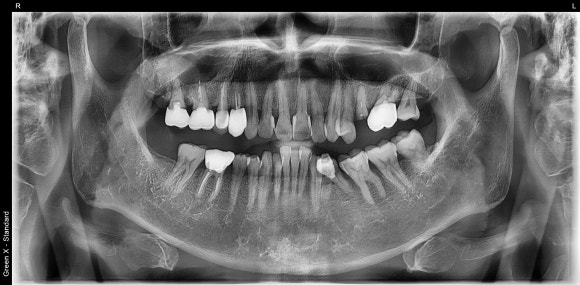

오늘 다룰 케이스는 어느 60대 남성 환자분의 이야기입니다.

구강건강상태가 동년배의 다른 환자분들에 비해 매우 양호하신 편이십니다.

그 흔한 임플란트도 한 번 해보시지 않으셨습니다.

20250304

그런데 이를 어쩌면 좋지요.

치아 하나가 동강이 나서 오셨습니다.

다행히 충치 때문은 아닌 것 같네요.

이렇게 건치로 오래 살아오신 분들중에

치아가 수십년에 걸친 하중을 견디지 못하고

스스로 파절되어 오시는 분들이 종종 계십니다.

경우에 따라 뽑아야할 때도 있고

운 좋게 살려서 쓸 수 있는 날도 있습니다.

이 분은 운좋은 편에 속합니다.

이유는 다음과 같습니다.

-

뿌리를 타고 내려가는 충치가 없다

뿌리의 길이가 그리 짧지 않다

뿌리 주위의 염증이나 골소실이 없다 (흔들림이없다)

씹는 힘을 그리 크게 받는 치아가 아니다 (어금니가 아님)

반대의 경우라면 발치로 이어질 가능성이 높겠죠.